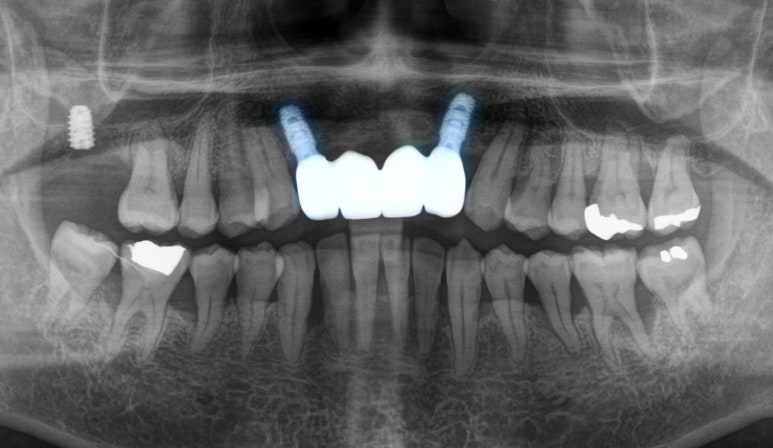

파노라마를 살펴보면

유지 장치를 부착해둔 이들이 보입니다.

그런데 뿌리 끝으로 염증 소견도 있고

그리 건강해 보이지만은 않습니다.

아마도 위 아랫니가 지속적으로

닿으면서 자극이 되고,

계속된 스트레스와 함께 잇몸뼈에도

영향을 준 것 같습니다.

환자께서 비용 부담이 있으셨기에

임플란트는 2개만 심고

4개의 크라운을 연결한

브릿지로 제작하였으며,

윗니가 아랫니를 덮을 수 있는 형태로

수복해 드렸습니다.